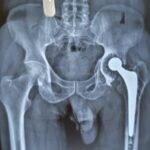

Revision knee replacement surgery is performed when a previously replaced knee joint develops problems such as pain, instability, stiffness, infection, implant loosening, or wear over time.

In this procedure, part or all of the existing knee implant is removed and replaced with new components to restore knee function and reduce pain.

Revision surgery is more complex than primary knee replacement and requires careful planning and expertise. The goal is to improve stability, alignment, and mobility of the knee, helping patients return to comfortable daily activities.